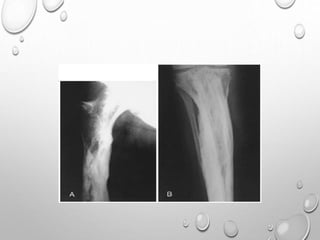

RADIOLOGY :

DIFFUSE DECREASE IN BONE DENSITY , PENCIL THIN CORTEX , MULTIPLE FRACTURES

, WRINKLED CONTOUR ANGULATION.

BONES MAY BE - THIN AND GRACILE….MOST COMMON

SHORT , THICK DUE TO FRACTURE DEFORMITY

EXTREMITY – LL > UL

MULTIPLE FRACTURE SOFTEN TRANSVERSE

HEALING WITH TUMORAL CALLUS FORMATION